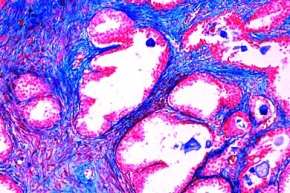

Mikropräparat - Adenomatöse Prostatahypertrophie

12,14 €

inkl. 19 % USt zzgl. Versandkosten

Zum Artikel